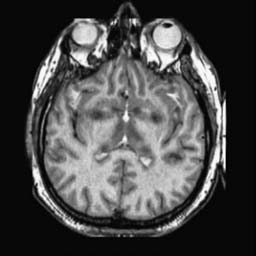

To demonstrate the effectiveness and efficiency of the proposed image fusion method , we conduct a set of comparative experiments on three image datasets. The first is composed by 8 pairs of multi-modal medical images and the second one contains 15 pairs of multi-focus gray or color natural images. These two datasets are often used in many related papers and some examples are shown in Figure 3(a) and Figure 3(b). The third one is a new multi-focus cervical cell image dataset collected by ourselves, which consists of 15 groups of color images and each group contains a series of multi-focus cervix cell images with size of or , etc. Some source examples are shown in Figure 3(c). Our source code implemented in C++ along with the new multi-focus cervical cell image dataset is available online.

We first evaluate the performance of the proposed method under varying total number of octaves and number of layers sampled per octave. The fused images of a pair of multi-modal medical images with different and are shown in Figure 4. In this example, on the one hand, when only 1 or 2 octaves are involved in constructing the DoG pyramid, the fused images fail to keep the integrity information of large size objects (e.g. eyeballs), while by increasing the value of , the integrity information of eyeballs is preserved. On the other hand, although not as significant as the increase of octave numbers , the fused image can contain more details by the increase of layer numbers . The corresponding objective quality metrics are shown in Figure 5. As shown in Figure 5(a), most of the metric values are improved as the number of octaves increases with the fixed layer numbers 3 in the global tendency and each of them tends to be stable when the number of octaves is 5. To get a relatively good quality from Figure 5(b), we can notice that some of the metric values can get a good performance when the number of layers is 3, such as the MI, SSIM, QI and VIF, though there are only a little change of all the metric values by increasing the number of layers with the fixed octave numbers 5. Because it will result in more computation burden with the increase of the value and , and for different kinds of source images, there are different performance with the diverse parameter settings. To get a trade-off between them in our experiments, we set for the multi-modal dataset, for the natural datasets and for the multi-focus cell dataset, respectively.

Figure 6 shows the fused images obtained by different methods with the multi-modal source images shown in Figure 3(a). As shown in these figures, the proposed method can produce images which preserve the complementary information of different source images well. Moreover, due to the scale-invariant structure saliency selection, our method can keep the integrity information of large size objects and the visual details simultaneously. Although the fused image generated by other methods can also capture the details to some extent, all of them fail to keep the integrity information of large size objects such as the eyeballs. Furthermore, from Figure 6(k)-6(t), the DTCWT, GFF, IM and NSCT methods may decrease the brightness and contrast while the proposed method can preserve these features and details without producing visible artifacts and brightness distortions.